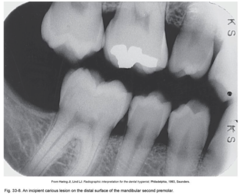

interproximal incipient caries

Front

Back